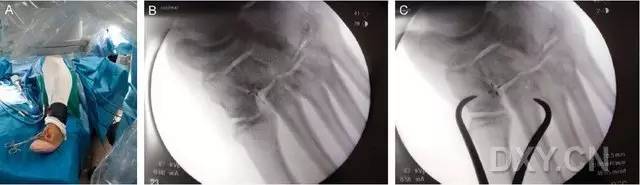

应用一把大号持骨钳把持固定于第 2 跖骨基底外侧面(经原手术切口或在该部位做一小切口,然后钝性分离、显露第 2 跖骨外侧面骨质)和内侧楔骨内侧面(在该部位做一小切口,然后钝性分离、显露内侧楔骨内侧面骨质)之间,以维持复位(图 3)。

图 3. 术中 X 线透视下,在中足经 Lisfranc 关节置入持骨钳,以维持固定损伤复位

完成术区暴露和维持复位后,在 X 线透视下,自足底方向经第 2 跖骨基底背外侧向内侧楔骨置入导针,采用空心钻经导针钻孔,然后将一枚 4.0-5.0 mm 直径适当长度的半螺纹空心螺钉经导针置入(图 4)。

图 4. 术中 X 线透视下,经第 2 跖骨基底背外侧向内侧楔骨置入 Lisfranc 螺钉